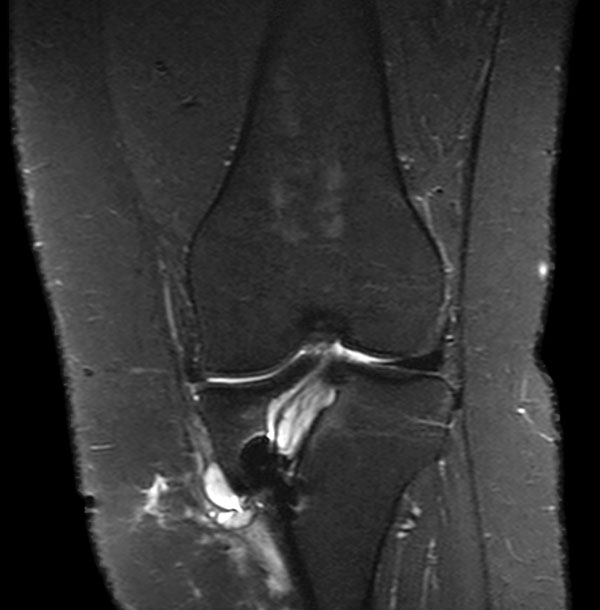

Coronal PDw SPAIR